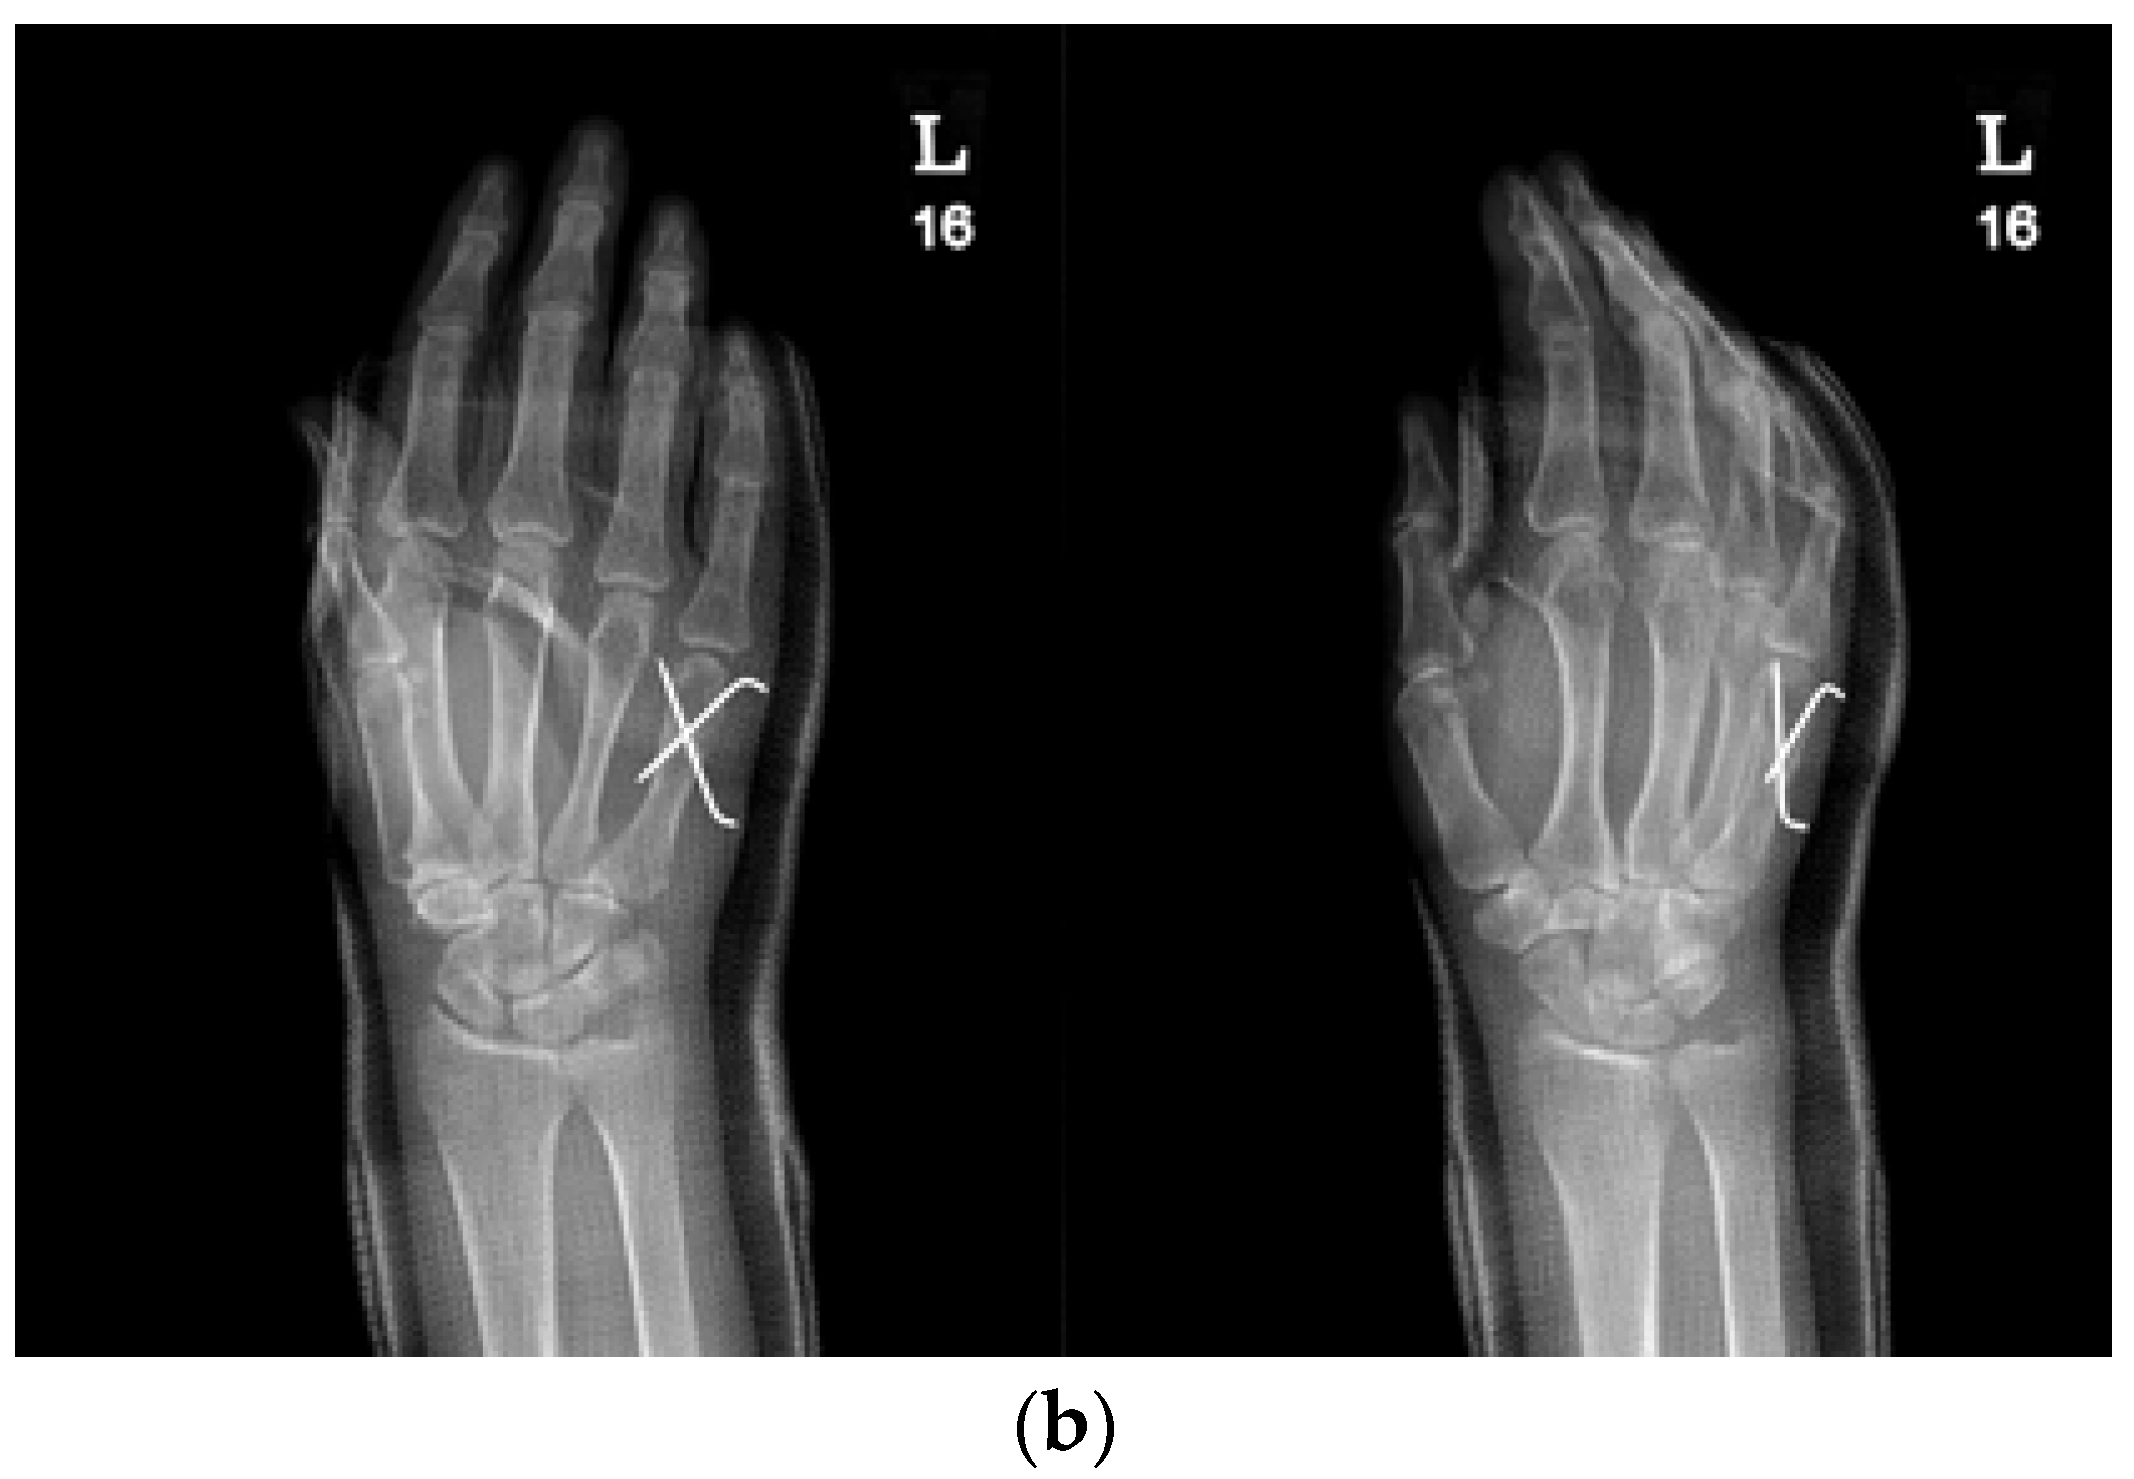

The KP method involved the insertion of two K-wires across the fracture site to stabilize the fracture. The number and size of K-wires used were determined based on the surgeon’s preference and the specific characteristics of the fracture (Figure 1a,b).

Figure 1.

(a) Radiograph of a 70-year-old female patient with displaced little-finger metacarpal neck fracture of the left hand. (b) Radiograph of a 70-year-old female patient who underwent the KP method using two K-wires.